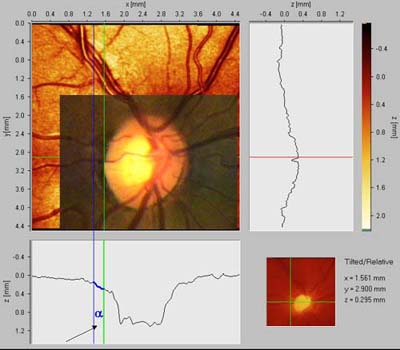

Peripapilární atrofie

Před 100 lety Elschnig a Bucklers rozpoznali souvislost mezi peripapilární atrofií a glaukomem a cirkulární peripapilární atrofii v pozdních stadiích glaukomové neuropathie nazvali "halo glaucomatosus". Oftalmoskopicky jsou patrné dvě zóny: beta je centrální, alfa periferní.

Zóna ALFA:

nepravidelná hypo a hyperepigmentace a ztenčení chorioretinální tkáně. Je projevem nepravidelností pigmentu retinálního pigmentového epitelu. Způsobuje relativní skotom.

Zóna BETA:

je světlejší zóna s viditelnou sklérou a velkými cévami cévnatky.

Nepřímá úměra jejího rozsahu k výši nitroočního tlaku: Čím vyšší tenze, tím menší atrofie. Čím nižší tenze, tím větší atrofie.